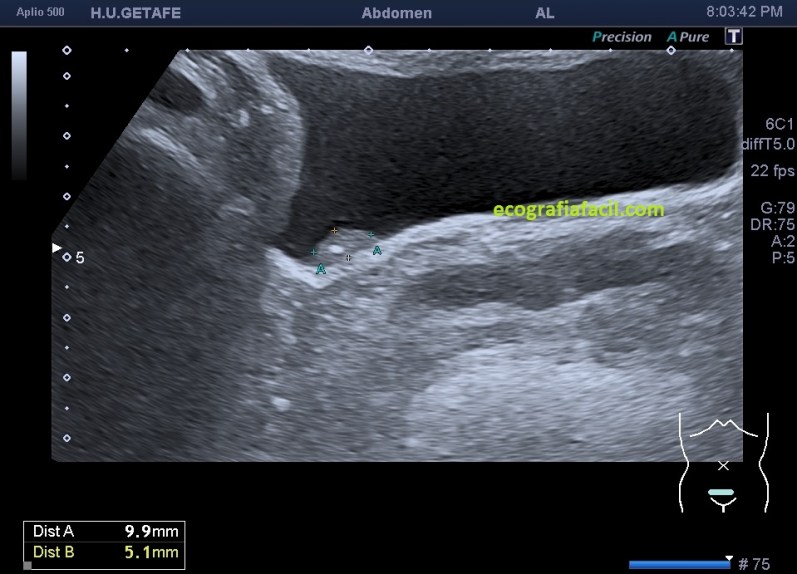

La imagen 2,3,4 y 5 demuestran una lesión de pared vesical, ovalada, hiperecogénica, muy pequeña, con un calcio en su interior (flecha amarilla), pequeña para poder demostrar vascularización, sospecha en el informe de tumor maligno de vejiga, el paciente entra en circuito de neoplasia precoz. A las pocas semanas fue operado, no hizo falta quitarle la vejiga. La detección fue en este caso, vital.

Observa como cambia todo entre la imagen 1 y 2, marcando la flecha amarilla el mismo lugar y la variación sustancial de como se ve una lesión en una vejiga distendida y en otra que no lo está, ojo que estas situaciones son cotidianas y el paciente puede ser asintomático.